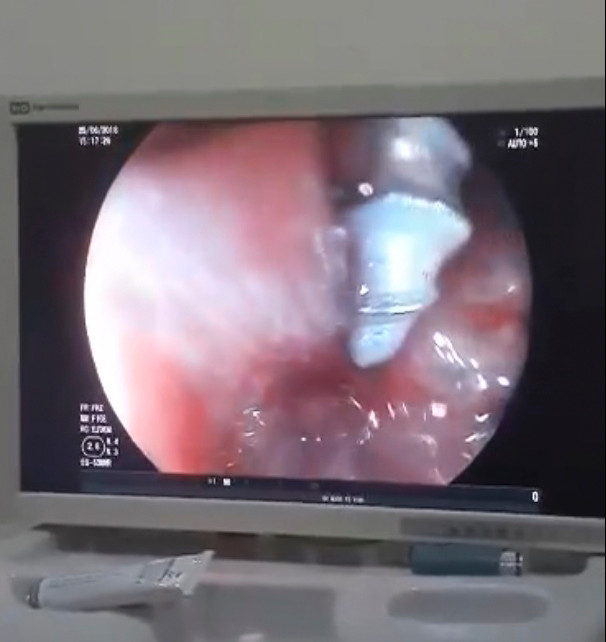

Hình ảnh dị vật quan sát được khi nội soi

Hình ảnh dị vật quan sát được khi nội soi